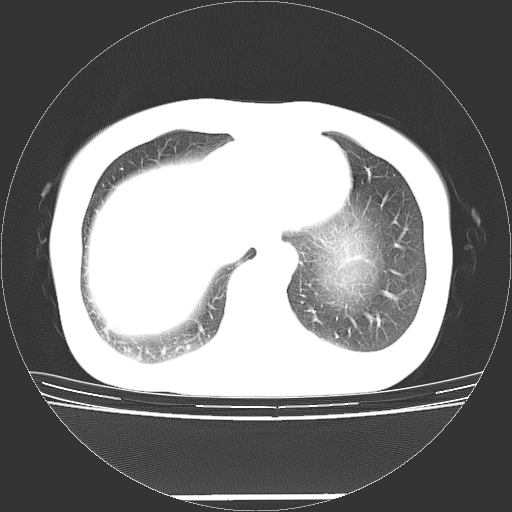

标题: CT27224:女,43岁,体检发现左肺下叶结节影。 [打印本页]

女,43岁,体检发现左肺下叶结节影。

左下肺外带胸膜下见孤立实性均匀密度结节影,边缘光整,增强呈渐进性强化,病灶吴分叶征及毛刺征象;支持硬化性血管瘤。

左肺下叶基底段圆形结节,多考虑:错构瘤>硬化性血瘤>炎症假瘤>周围性肺癌!期待结果!

左肺下叶外侧基底段圆形结节,多考虑:错构瘤>硬化性血瘤>炎症假瘤>周围性肺癌!期待结果!